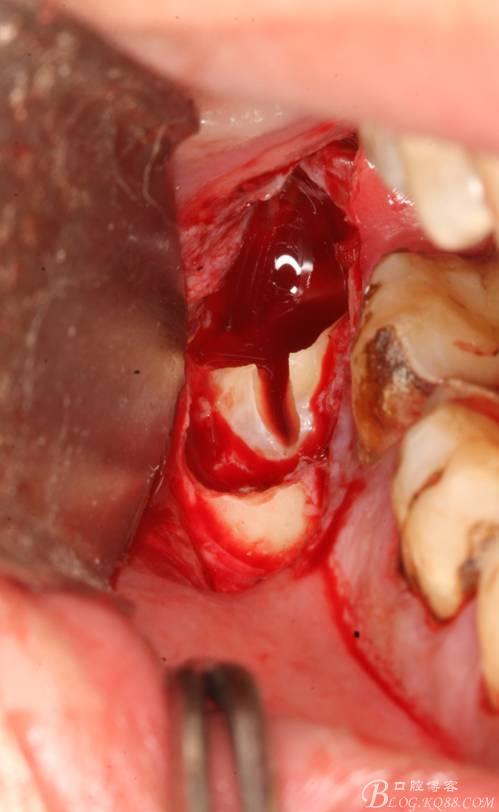

2.切開翻瓣

3.去骨、暴露48.

4. 縱分牙根和牙冠

5.取出牙根